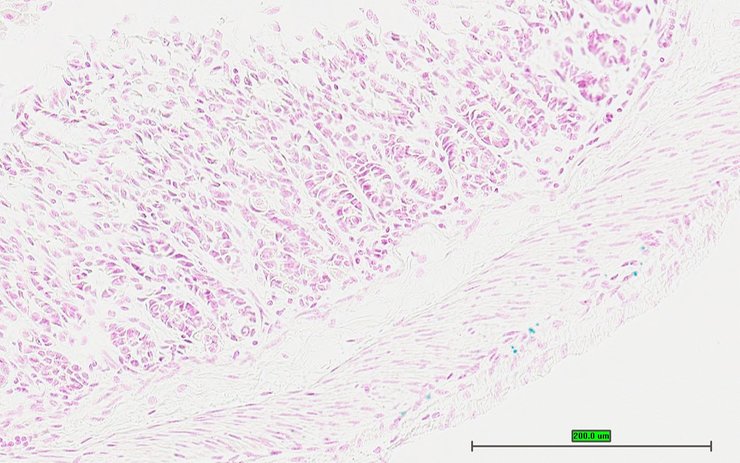

TS28: stomach Present UC Davis_1879388

Specimen UC Davis_1879389: postnatal adult; Cnga3tm1.1(KOMP)Vlcg/Cnga3+ (more )

Structure Level Pattern Image Note

TS28: stomach Present UC Davis_1879389